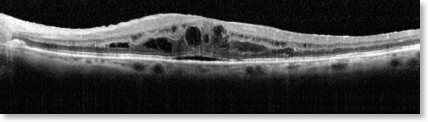

Stacks Image 50208

OCT-Bild der trockenen AMD: Ablagerungen (Drusen, „Müllpakete“ unter den Photorezeptoren), kein Ödem

Häufigkeit und Verlauf der trockenen AMD

Mit ca. 85 Prozent ist die trockene altersbedingte AMD die weitaus häufigste Form der AMD. Bei dieser Form kommt es über Jahre zur Ablagerung von Zellmüll unter die Schicht der Photorezeptoren und damit zum langsamen Verlust der Photorezeptoren, der lichtempfindlichen Zellen der Netzhaut des Auges, und somit zu einer langsamen Sehverschlechterung bei meist lang erhaltener Lesefähigkeit.